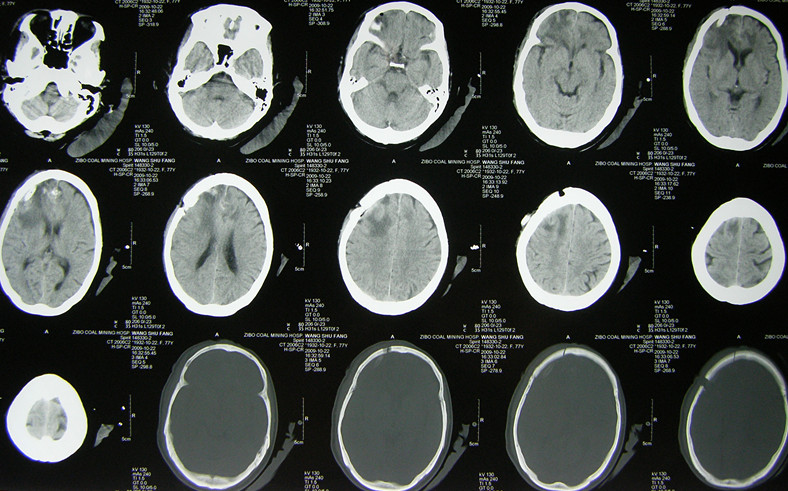

(1)注意识别脑瘤卒中的平扫CT及 MIR片特点:①多为形态不规则密度不均匀的混杂密度病灶,而高血压脑出血多为密度较均匀的类圆形团块状较高密度灶;② 病灶常位于远离中线的脑叶,而高血压脑出血的病灶常位于基底节区及丘脑区;③ 其病灶相对于高血压脑出血病灶的周围水肿比较明显,出血灶周围常有较广泛的大片脑水肿低密度区,而一般脑血肿周围常仅有薄的水肿带;见影像片1,2

影像片2:CT及MR比较

(2)增强扫描时,病灶局部可见增强肿块影,尤其是当非出血区强化则高度提示脑瘤卒中。因此,初次CT怀疑脑瘤卒中时,如果病情允许,建议复查CT及强化CT。MRI显示脑瘤卒中优于CT,若有条件最好做个MRI平扫加强化。见影像片3

影像片3:平扫及强化MRI比较。